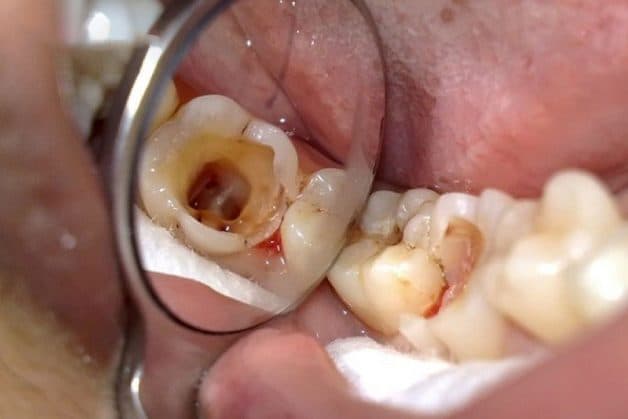

2.1 Bị sâu tình trạng nặng

Đầu tiên, bác sĩ sẽ thăm khám kỹ lỗ sâu răng xem có thể thực hiện hàn hay bọc sứ hay không, sau đó chỉ định nhổ mới được đưa ra. Nếu không điều trị sớm, lỗ sâu sẽ lây lan ra những răng bên cạnh và gây nên các bệnh lý răng miệng nguy hiểm.